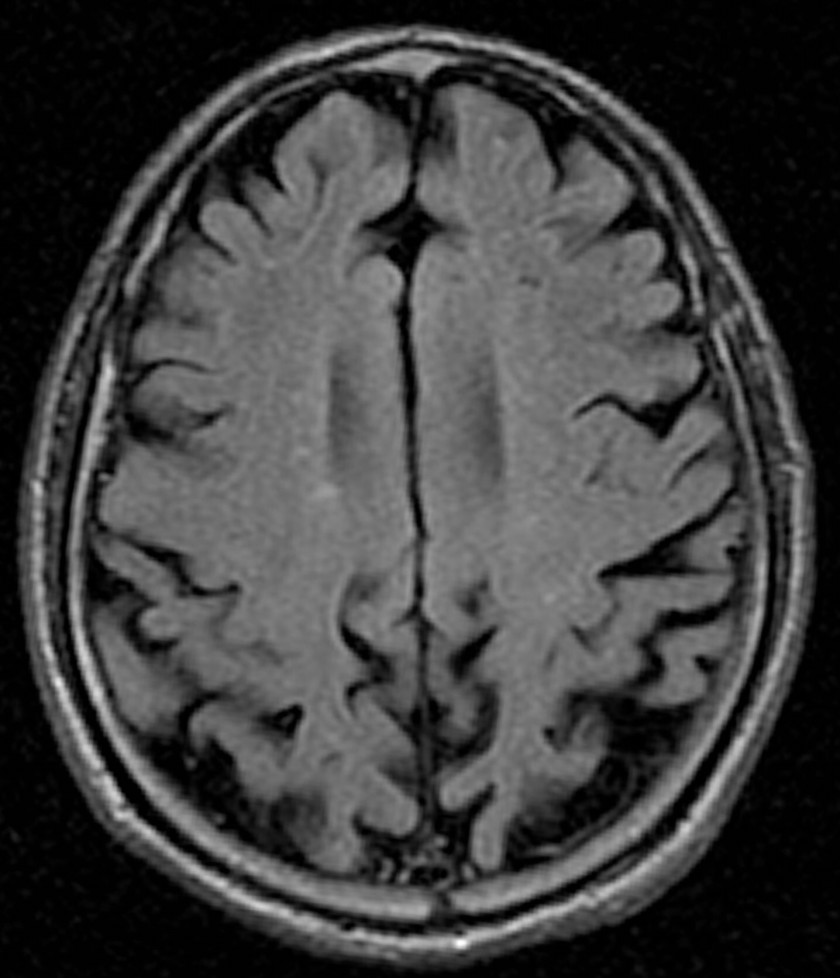

2018/09/18 MRIでも◯◯だから、CTなんて❌❌

もう、15年以上(もっとかも)、診療してきた80歳代 女性。お付き合いが長くなりました。

今回、ちょっとしたキッカケがあり、MRI撮影となりました。認知機能に問題なく、年に何回か(つい最近も)、海外に一人で行って来る方。長年の高血圧もあり、降圧剤を処方していますが、コントロール状況は良好。でも、最近の言動は昔より、何だか、自己否定的。鬱っぽい・・・。もともと、アタマの回転の良い方。御両親も、お子様も医療関係者。

色々な悩みも聞いてきたので、些細な言動でも、なんと無く気になる・・・。MRIの結果。前頭葉が萎縮している‼️

ピッ◯切痕がある‼️🤣医療で、絶対なんてあり得ない。そりゃ否定しません。が・・・この方の場合、自信をもって言えますが、

“一部の医者”が乱発しているピック病になるリスクはゼロでしょう。そもそも、ピック病が80歳代で発症なんて❓

🤣まぁ、そんなことは全く心配していません。さて、ココから本題。CTファン❓には申し訳ないが、MRIの撮影条件は上記のモノだけではありません。

上と同じ部位を異なる条件で撮影したのが以下。

異常が一目瞭然。白い部分が目立ちます。いわゆる、白質病変ですね。MRIを撮影しても、最初の条件のモノでは、診断できませんでした。では、CTだったら診断できましたか❓ゾッとしますね。各スライスをジッと見てみると、前頭葉の白質に白い部分が多いコトがわかりました。この所見は処方の参考にもなりました。なんとか、鬱っぽい状態から脱出させませんと。

もちろん、ノーサプリメントで。最後に。MRIでも完璧にはできないですが、CTで認知症診断なんてできますか❓

高血圧症例は可能な限り、MRI撮影をしてもらいましょう。

理由は何でも知っているあなたの主治医にお尋ねください。。